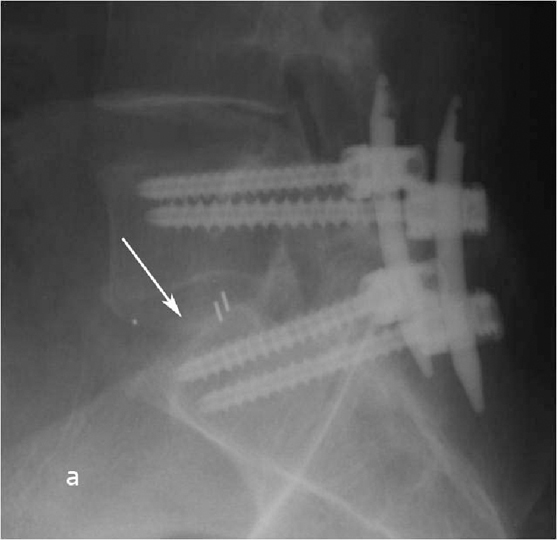

Рис. 9 a,b. Ренгенограмма поясничного отдела позвоночника в боковой (a) и прямой (b) проекции. Транспедикулярная фиксация L5-S1 позвонков титановой конструкцией канюлированными винтами, межтеловая фиксация позвонков кейджем из PEEK-керамики. Стрелкой указано положение ренген–негативного кейджа, видны титановые метки кейджа.

Рис. 10 a. Ренгенограмма поясничного отдела позвоночника в боковой (a) и прямой (b) проекции. Транспедикулярная фиксация L5-S1 позвонков титановой конструкцией канюлированными винтами, межтеловая фиксация позвонков кейджем из PEEK-керамики. Стрелкой указано положение ренген–негативного кейджа, видны титановые метки кейджа. Рис. 10 b. Ренгенограмма поясничного отдела позвоночника в боковой (a) и прямой (b) проекции. Транспедикулярная фиксация L5-S1 позвонков титановой конструкцией канюлированными винтами, межтеловая фиксация позвонков кейджем из PEEK-керамики. Стрелкой указано положение ренген–негативного кейджа, видны титановые метки кейджа.

При контрольной рентгенограмме отмечено правильное положение транспедикулярной системы и кейджа на уровне L5-S1 позвонков. (Рис.9)

Пациенту выполнено оперативное лечение: удаление секвестрированной парамедианной грыжи мп диска L5-S1 слева из минидоступа, миниинвазивная транспедикулярная фиксация L5-S1 титановой конструкцией.

На следующий день пациент отметил значительное уменьшение болей в левой ноге, мог ходить по палате. На 4-е сутки был выписан из стационара в удовлетворительном состоянии: болей в ноге не отмечал, сохранялась умеренная болезненность в области операционной раны, которая прошла через 3 недели.